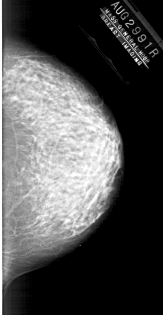

A_1878_1.RIGHT_MLO

RIGHT_MLO LINES 6241 PIXELS_PER_LINE 3046 BITS_PER_PIXEL 12 RESOLUTION 43.5 NON_OVERLAY